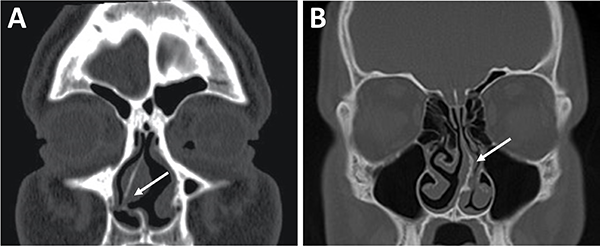

La principal utilización de la tomografía es la identificación de estructuras anatómicas óseas útiles a la hora de la planificación quirúrgica. Con una tomografía con reconstrucción 2D se pueden evidenciar con sencillas mediciones las siguientes características: septum nasal, variantes turbinales, presencia y posición de los ostiums esfenoidales, rostrum esfenoidal y su relación con el vómer, neumatización del seno esfenoidal, tabiques intrasinusales, distancia intercarotídea, grado de neumatización de etmoides posterior e identificación de nervios ópticos en su trayecto adyacente al seno esfenoidal.23,29

Respecto a los ostium esfenoidales, cabe destacar que son el punto de entrada óptimo al seno esfenoidal. En caso de ser dificultosa su localización (situación frecuente) se podría ingresar al seno esfenoidal aproximadamente 1,5 cm por encima del borde superior de la coana (fig. 11).23,13

El grado de neumatización de etmoides posterior es variable. Se debe identificar si existe hiperneumatización del mismo, con extensión de celdillas a región superior y lateral se seno esfenoidal, variante que conocemos como celdas de Onodi. Su relevancia radica en mantener durante el intraoperatorio un adecuado corredor hacia la hipófisis, y evitar una “falsa vía”, con potencial lesión intracraneal (fig. 15).